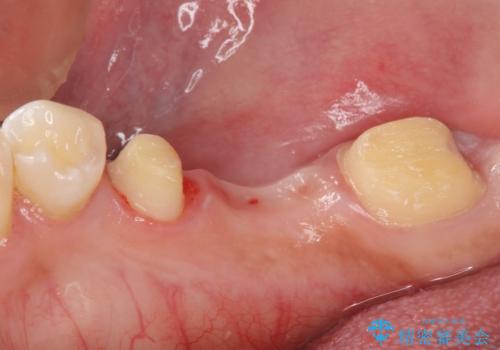

金属ブリッジを除去し、虫歯を完全に除去し、形を整え、

精度の高いシリコーン材料にて型どりをしました。